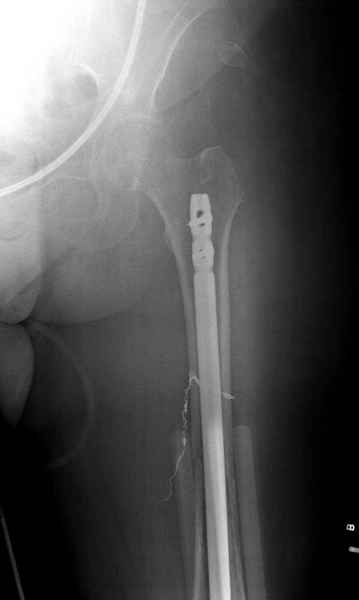

Известно, что многие из нас независимо от метода лечения и стадии первичной опухоли проводят интрамедуллярное штифтование при различных патологических состояниях бедра, включая патологические переломы.

Со слов, больная ничем не болела, только последние 3 месяцев чувствовала боли в бедренной области. КТ брюшной полости подтвердил увеличенную правую почку. (5-6)

Для предупреждения кровотечения во время рассверливания, за день до операции провели эмболизацию сосудов питающий метастаз. http://radiology.rsnajnls.org/cgi/reprint/150/3/673.pdf (7-11, 12-15-16)

С минимальным рассверливанием и ретроградным методом провели остеосинтез бедра 12 мм гвоздем. (17-20)

Кровопотеря во время операции меньше 100 мл.